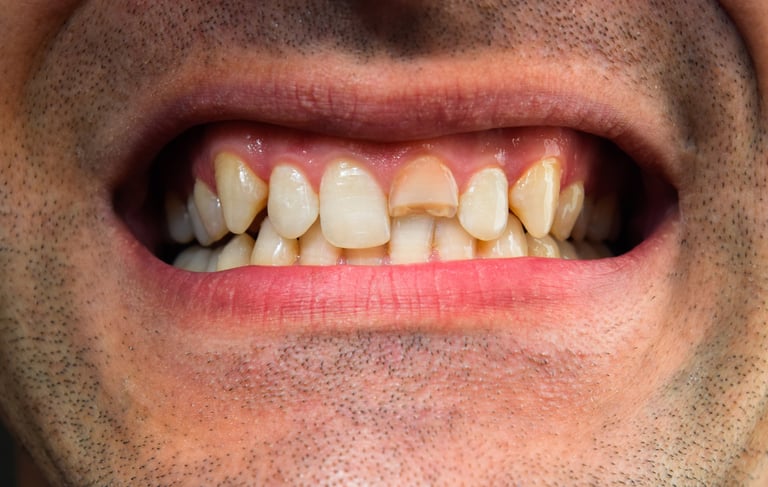

Se revisa si hay fracturas en la parte visible del diente. Las fracturas de la corona pueden ser causadas por trauma o caries extensas y pueden afectar el tratamiento endodóntico.

Evaluación de fracturas de la corona